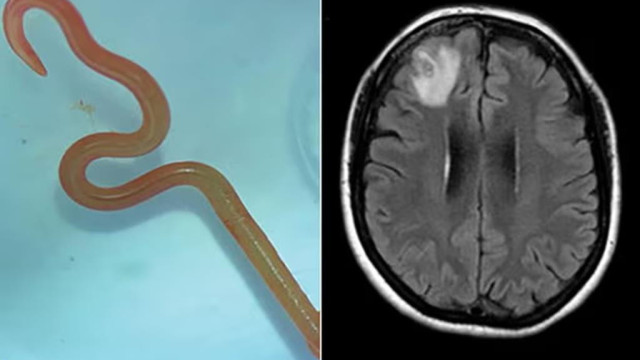

O neurocirurgião, Dr. Hari Priya Bandi, retirou um verme parasita de 8 centímetros de comprimento do cérebro de uma paciente, o que a levou a procurar Senanayake e outros colegas do hospital para obter conselhos sobre o que fazer a seguir.

Segundo informações, a paciente já tinha sido internada em janeiro de 2021 com queixas de febre, dores abdominais e diarreia incessantes, tosse seca e suores noturnos. Em 2022, a estes sintomas juntaram-se sinais de depressão e perda de memória, o que levou ao seu encaminhamento para o hospital de Canberra. Feita uma ressonância magnética que revelava algumas anomalias, a mulher foi operada ao cérebro.

Ophidascaris robertsi é um verme geralmente encontrada em cobras pítons e a paciente do hospital de Canberra marca o primeiro caso mundial do parasita encontrado em humanos.